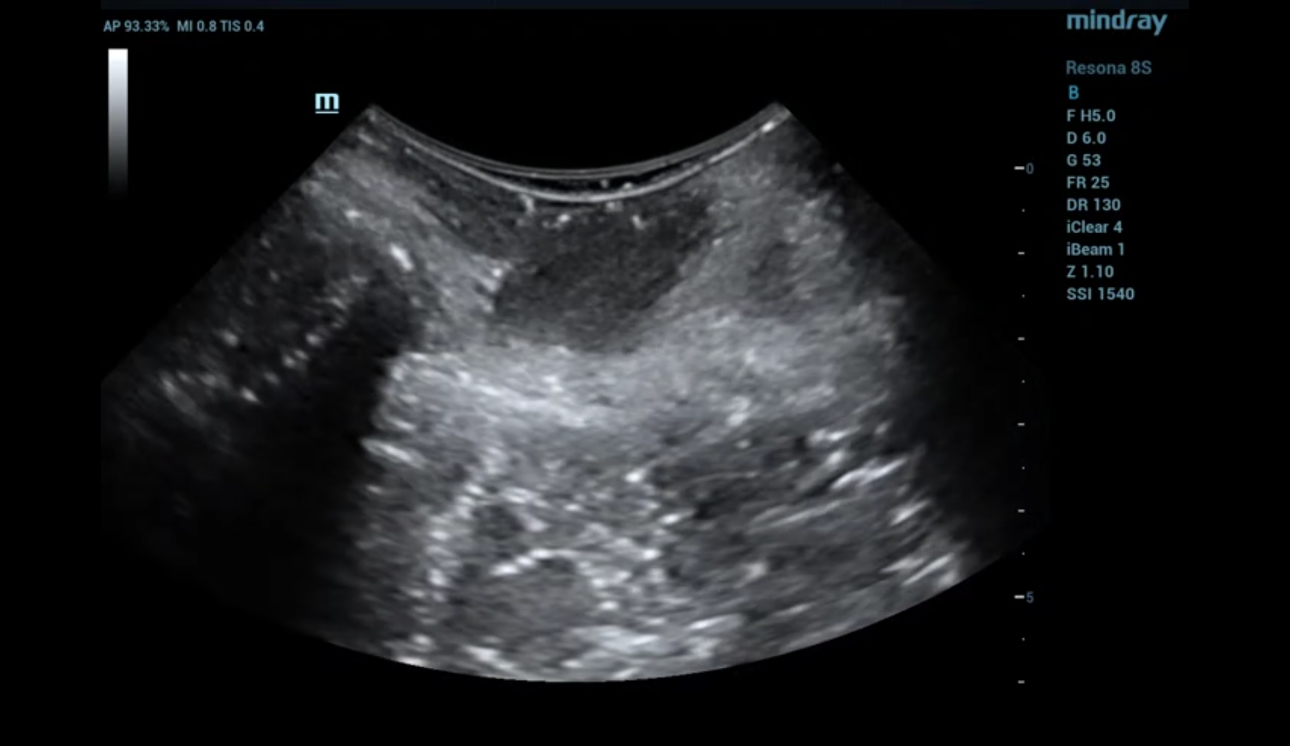

levator-trauma-fig5-pc

형상 3. 좌측 avulsion의 볼륨 이미징